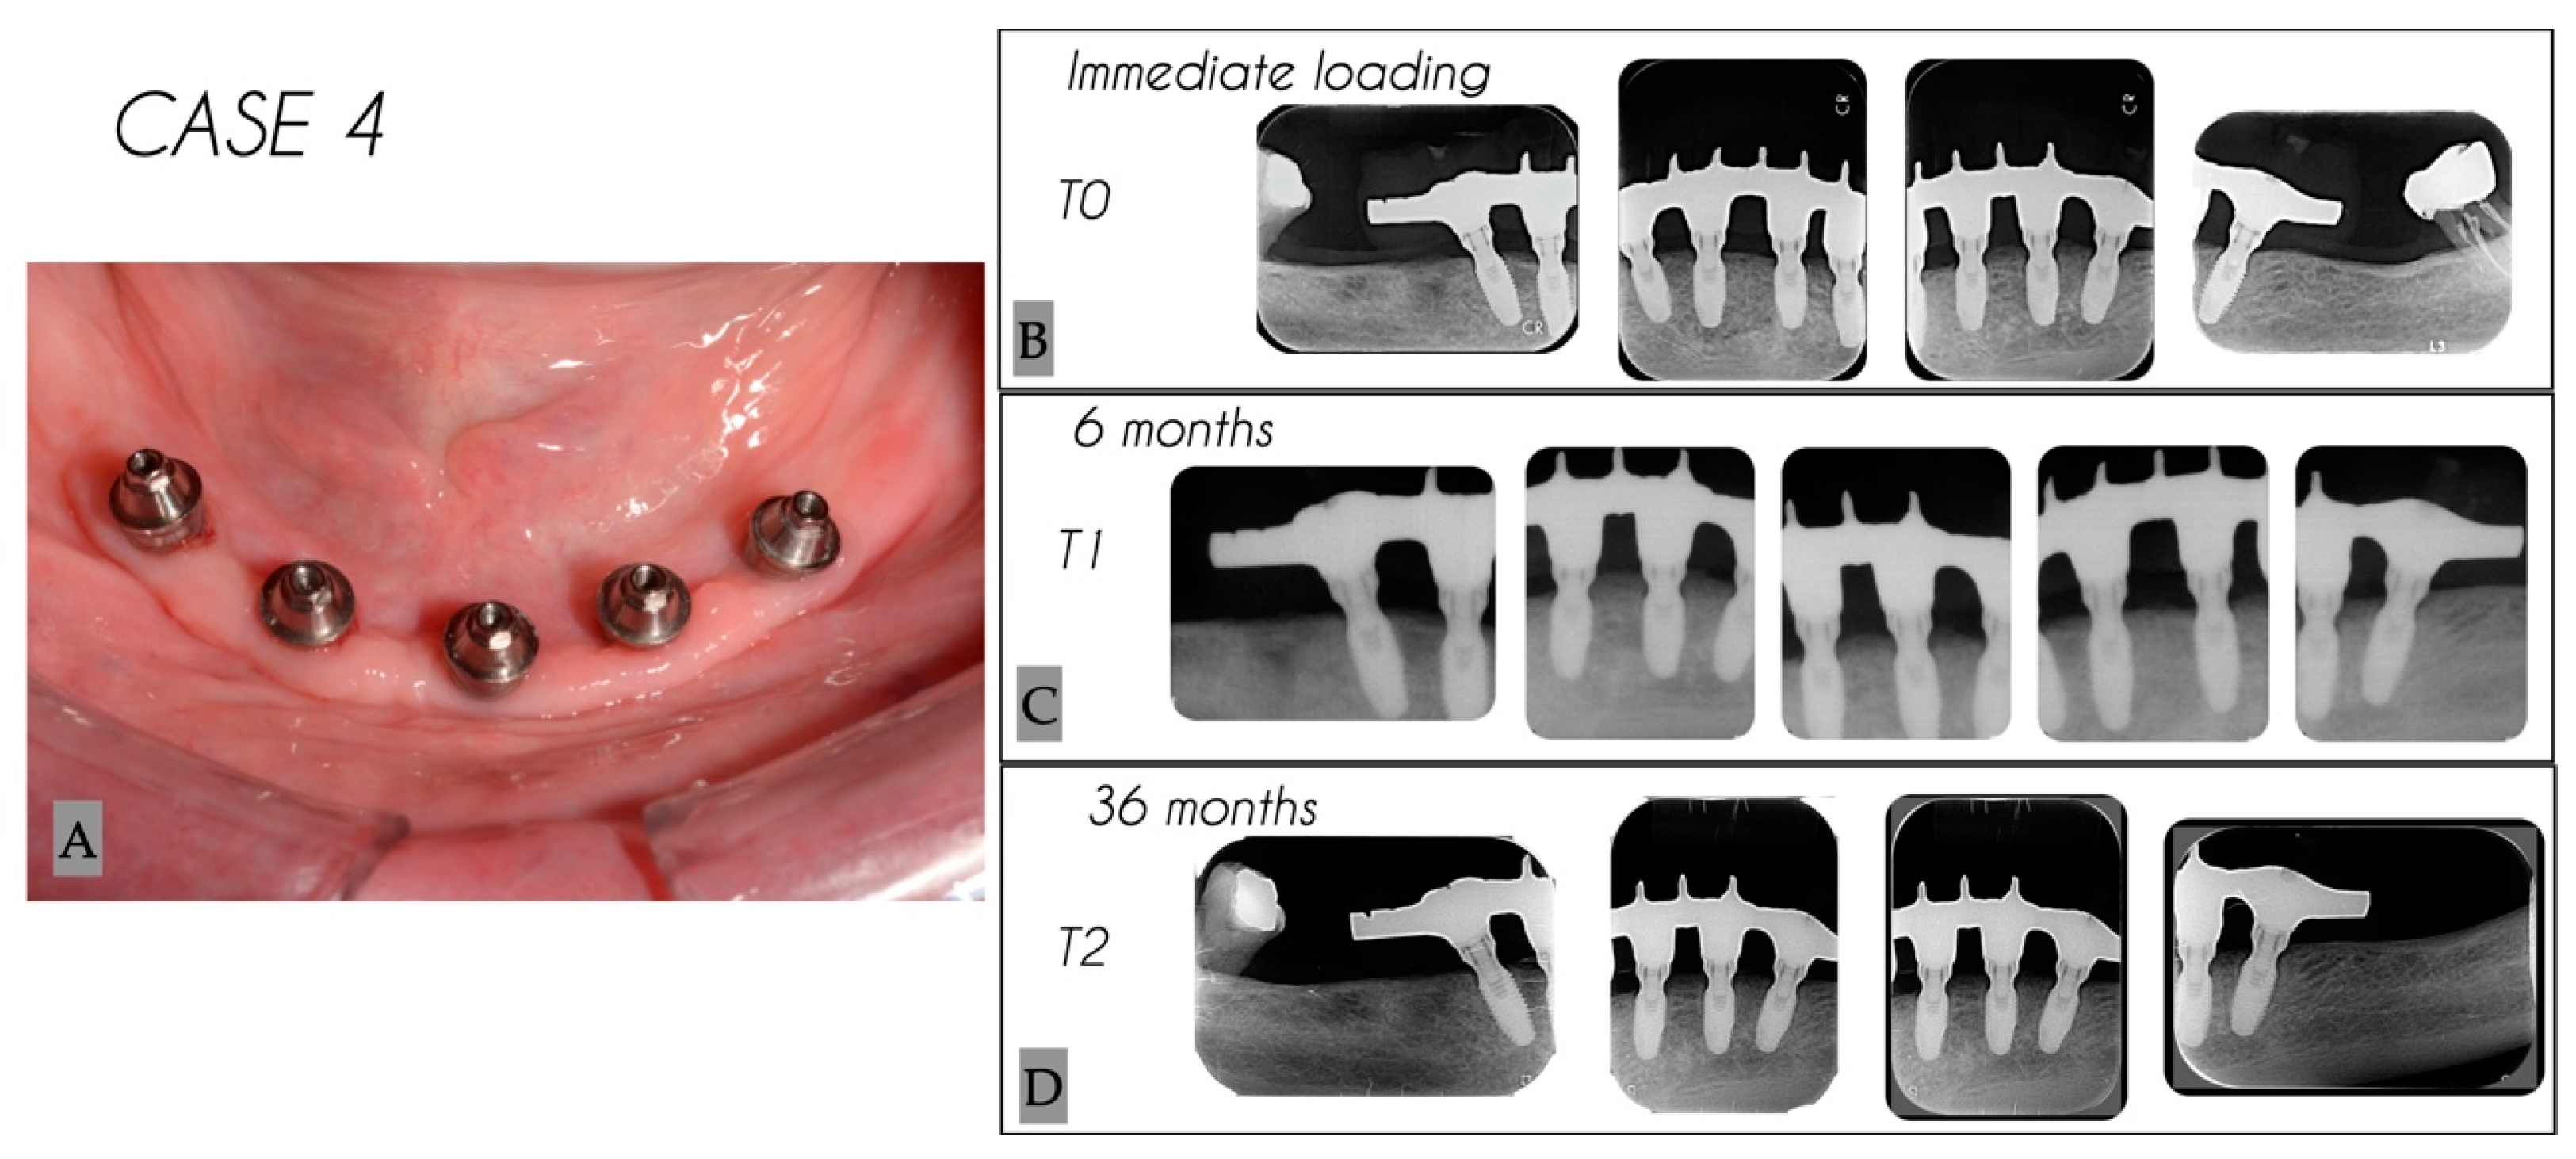

| Case No. | Tooth No. | Initial MBL (mm) | MBL 6 Months (mm) | MBL 36 Months (mm) | KM 6 Months (mm) | KM 36 Months (mm) |

|---|---|---|---|---|---|---|

| 4 | 35 | 0.54 | 1.22 | 1.35 | 4 | 4 |

| 4 | 31 | 0.58 | 1.01 | 1.07 | 4 | 4 |

| 4 | 33 | 0.84 | 1.45 | 1.6 | 5 | 5 |

| 4 | 43 | 0.57 | 1.18 | 1.67 | 4 | 4 |

| 4 | 45 | 0.47 | 1.98 | 2.17 | 4 | 4 |

| Mean | 0.60 | 1.37 | 1.57 | 4.2 | 4.2 | |